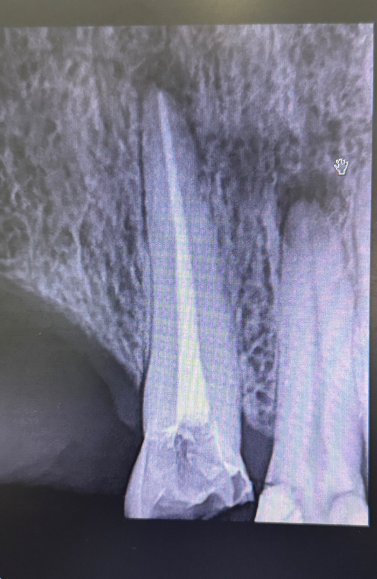

Root Canal Treatment

Root canal treatment (RCT) is a procedure used to save a tooth that’s infected, cracked, or damaged. By removing the infected pulp inside the tooth, cleaning and shaping the canals, and sealing it with a safe material, RCT preserves your natural tooth instead of resorting to extraction.

The procedure is straightforward: your dentist numbs the area, cleans out the infection, and seals the tooth for long-term protection. A crown or composite build-up is often placed afterward to strengthen and restore the tooth fully.

Root canal treatment not only relieves pain and infection but also maintains your oral health and keeps your natural smile intact.

Experiencing tooth pain or sensitivity? Schedule an appointment today to see if root canal treatment can save your tooth.

Root Canal Treatment